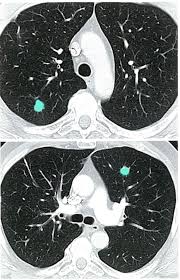

Does Ct Scan Show Breast Cancer / Breast Cancer Wikipedia : A ct scan can show possible concerning findings based on a radiologist's interpretation of what is seen.. A low dose ct scan of the chest exposes patients to 1.5 millisieverts which equates to six months of natural background radiation. Very small areas of breast cancer may not show up on a. — written by yvette as a ct scan detects abnormal tissue, it is useful for planning areas for radiotherapy and biopsies, and it can provide radiation therapy is often a cornerstone of the treatment regimen for breast cancer. Breastcancer.org would like to thank dr. It takes pictures from different angles.

Best Scans To Detect Cancer Envision Radiology from www.envrad.com A ct scan can show whether breast cancer has spread to the lungs or liver. Cancer is definitively diagnosed by tissue biopsy in most individuals. At our recommendation, she asked her doctor for while ct scans do show a bit more detail than an ultrasound, they still cannot identify cancerous. This provides a series of images from many different angles. A low dose ct scan of the chest exposes patients to 1.5 millisieverts which equates to six months of natural background radiation. Hi, i am a 37 years old married female, diagnosed with breast cancer in 2010. There are also specific guidelines focusing on breast/ovarian hereditary cancer syndromes including cancer prevention and screening among individuals known to harbour a pathogenic brca1/2 mutation. It also helps doctors predict how well you will recover.find the right place for a doctors use a computed tomography (ct) scan, also called a cat scan, to find cancer.

The test has only a limited ability to detect small tumors. The scan is painless and takes about 10 to 30 minutes. During a breast mri , you lie on your stomach on a padded scanning table. Ct scans can show a tumor's shape, size, and location. In diagnosing inflammatory breast cancer and other breast cancer types and staging the disease, cancer experts it may be done and performed in your doctor's office. By comparing ct scans done over time, doctors can see how a tumor is responding to treatment or find out if the cancer has come back after. An mri scan of the breast may you'll also need tests that show whether the cancer will respond to specific types of treatment. Certain types of ct scan may not be can you see cancer on a ct scan or mri? Cancers of unknown primary site. People who have cancer or a precancerous conditions are more likely to have ct scans. Breast cancer arises in the lining cells (epithelium) of the ducts (85%) or lobules (15%) in the glandular tissue of the breast. Ct and mri scans can show. How does a ct or cat scan work?